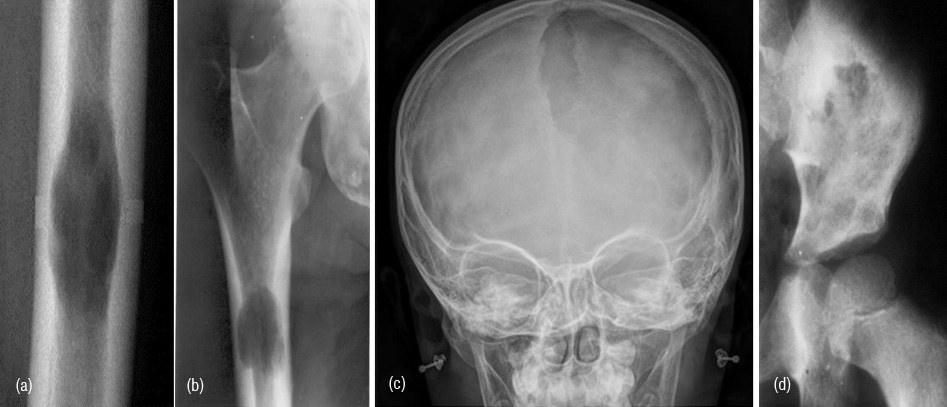

Bone infarcts

Old healed infarcts in the metaphyseal region of long bones simulate enchondroma. However, the radiological findings of an elongated lesion with serpentine calcifications and the peripherial fibroosseious membrane differentiates it from enchondroma (Figure 18abc). Occasionally the appearance may be similar to osteosarcoma (Figure 18d).

Figure 18: (a) Enchondroma, (b) Calcified infarct, (c) Calcified infarct in lateral view, (d) Osteosarcoma simulating infarct.